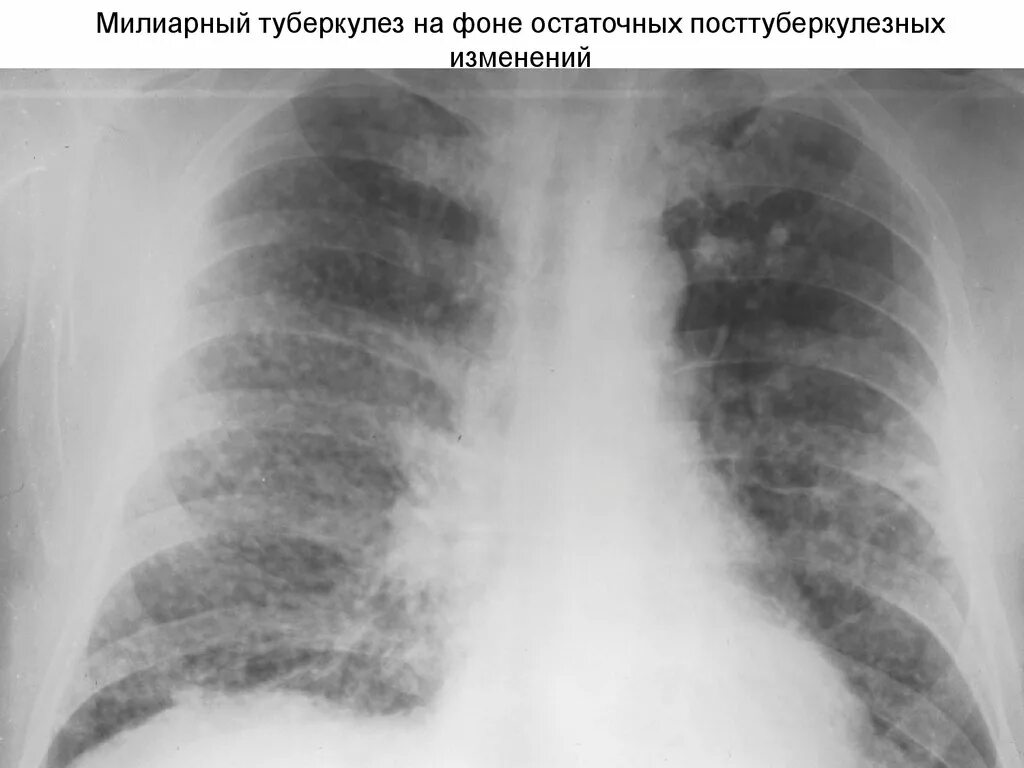

Изменения в легких